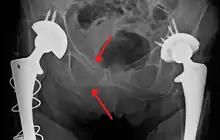

Blunt pelvic trauma

The most common causes of blunt pelvic trauma are motor vehicle accidents and multiple-story falls, and thus pelvic injuries are commonly associated with additional traumatic injuries in other locations.[28] In the pelvis specifically, the structures at risk include the pelvic bones, the proximal femur, major blood vessels such as the iliac arteries, the urinary tract, reproductive organs, and the rectum.[29][28]

.png.webp)

One of the primary concerns is the risk of pelvic fracture, which itself is associated with a myriad of complications including bleeding, damage to the urethra and bladder, and nerve damage.[30] If pelvic trauma is suspected, emergency medical services personnel may place a pelvic binder on patients to stabilize the patient's pelvis and prevent further damage to these structures while patients are transported to a hospital. During the evaluation of trauma patients in an emergency department, the stability of the pelvis is typically assessed by the healthcare provider to determine whether fracture may have occurred. Providers may then decide to order imaging such as an X-ray or CT scan to detect fractures; however, if there is concern for life-threatening bleeding, patients should receive an X-ray of the pelvis.[31] Following initial treatment of the patient, fractures may need to be treated surgically if significant, while some minor fractures may heal without requiring surgery.[28]

A life-threatening concern is hemorrhage, which may result from damage to the aorta, iliac arteries or veins in the pelvis. The majority of bleeding due to pelvic trauma is due to injury to the veins.[32] Fluid (often blood) may be detected in the pelvis via ultrasound during the FAST scan that is often performed following traumatic accidents. Should a patient appear hemodynamically unstable in the absence of obvious blood on the FAST scan, there may be concern for bleeding into the retroperitoneal space, known as retroperitoneal hematoma. Stopping the bleeding may require endovascular intervention or surgery, depending on the location and severity.[29]